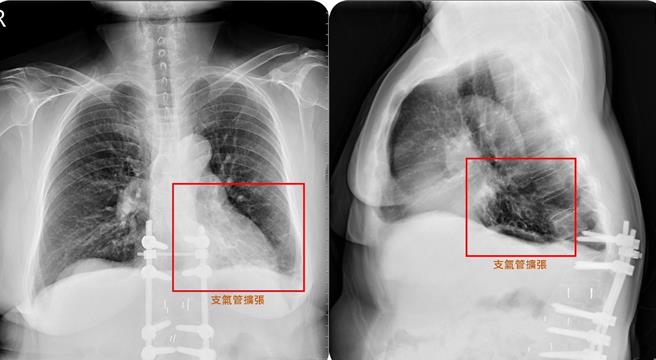

58岁简女士从未抽菸,数月前却突然久咳不停,痰液浓稠偏黄且带有血丝,近日变本加厉且合併发烧、食欲受影响。经就医发现,她的左肺支气管粗大,被痰塞满,是支气管扩张症惹祸,幸经药物及呼吸復健1个多月,症状大幅改善。

谢逸安指出,支气管扩张症主要是肺部支气管壁因为先天(基因)或后天原因导致结构破坏,小支气管失去弹性弯曲及扩张,形成永久不可逆的扩张,导致痰液堆积,而支气管壁上负责执行痰液清洁的纤毛,也因反覆发炎遭到破坏。